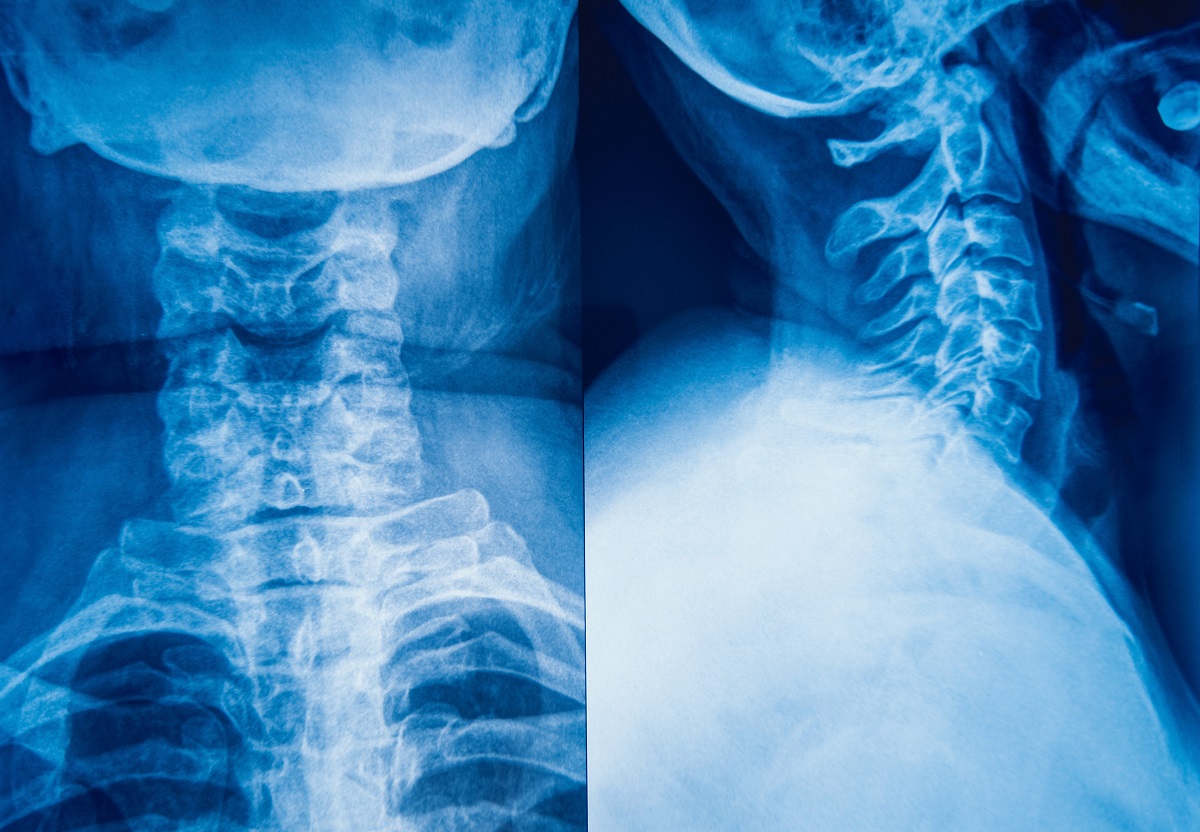

Основные симптомы со стороны опорно-двигательного аппарата

Повреждение аксиального скелета подразумевает болевой дискомфорт, выраженная тугоподвижность в шейном, грудном, пояснично-крестцовом сегментах хребта.

• Искривление осанки, укорочение позвоночной оси.

Со временем двигательная дисфункция нарастает, меняется естественный изгиб хребта, голова опускается, усугубляется сутулость. При желании повернуться в сторону необходимо задействовать весь корпус, в не одну шею. Ноги немного согнуты в коленях.

Инструментальные методы исследования включают рентгенографию позвоночной оси, крестца. Специалист внимательно изучает снимки, обращая внимание на крестцово-подвздошную область. При первой стадии проявляется нечеткость контуров сустава. Наличие эрозивных дефектов свидетельствует о второй стадии. При третьей стадии отмечается неполное сращение эластичных структур, при четвертой — полное.

Магнитно-резонансное сканирование крестцово-подвздошных сочленений, пояснично-крестцового отдела помогает выявить ранние изменения целевой зоны. Благодаря компьютерной томографии определяются деформация костных элементов, эрозивные дефекты сочленений.